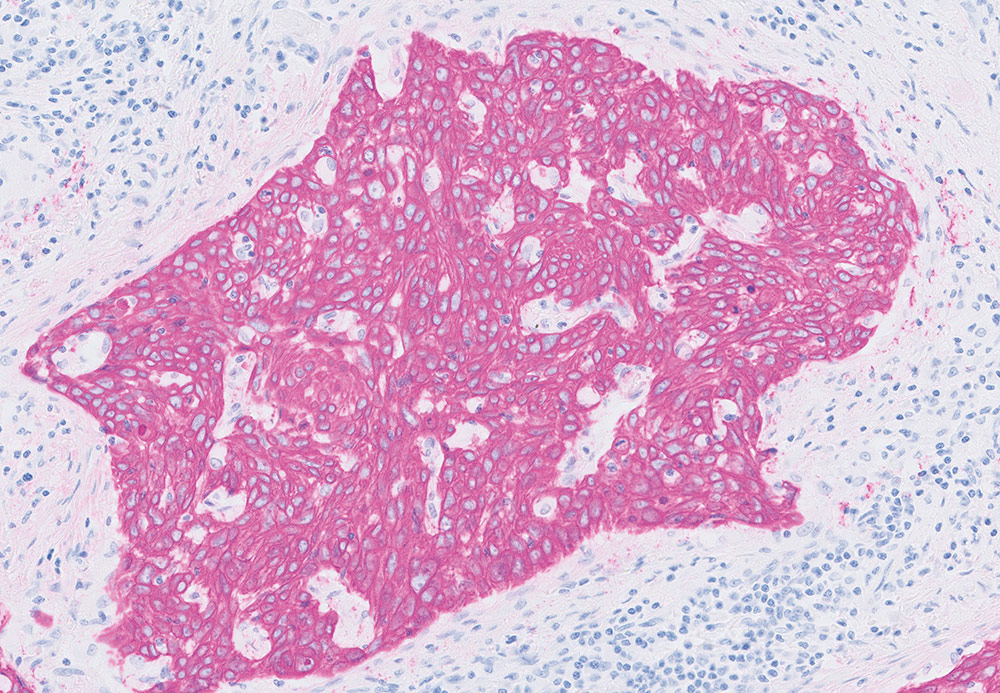

When diagnosing cancer, pathologists typically stain tumor samples with a brown stain called DAB. However, for skin and lung biopsies, they usually choose a red stain as it contrasts well with the brown melanin color in skin, and any pollution artifacts that are typical in lung tissue.

HRP Magenta has a transparent nature, yet is clearly visible, distinct and intense. This allows the pathologist to recognize tissue structures and cellular details even in strongly stained cases. Nuclei can be easily identified, and all details are visible.

HRP Magenta, used with the Dako EnVision FLEX visualization system for Dako Omnis, enables laboratories to stain with two colors—brown and magenta—occupying only few additional vial spaces in the instrument. This added flexibility is expected to enable a leaner workflow with quicker turnaround times for faster patient diagnoses.